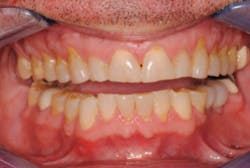

CASE PRESENTATION: A 55-year-old male airline pilot and former US Air Force fighter pilot presented to our practice with severe wear into dentin throughout his entire dentition. He had been wearing a night guard for at least 20 years. He was aware of his grinding habit, but did not report any pain in his muscles. His joints could be loaded comfortably. He did not report any history of joint clicking, and there was no evidence of internal derangement. His point of initial contact in centric relation (CR) was 15/18.

Both teeth had been restored with porcelain-fused-to-metal crowns. The lower crown had lost all of the occlusal porcelain and was fractured down to the metal coping. He had more than a millimeter slide from CR to his maximum intercuspal position with 1 mm of mobility in tooth No. 10. We measured 4 mm of horizontal overjet with mild crowding on the mandibular anterior teeth (figures 1 and 2). He was within normal limits when evaluating his profile with Arnett's true vertical line, Rickett's E plane, and his nasiolabial angle (100 degrees). (1-3)

Figure 1: Before treatment

Figure 2: Before treatment